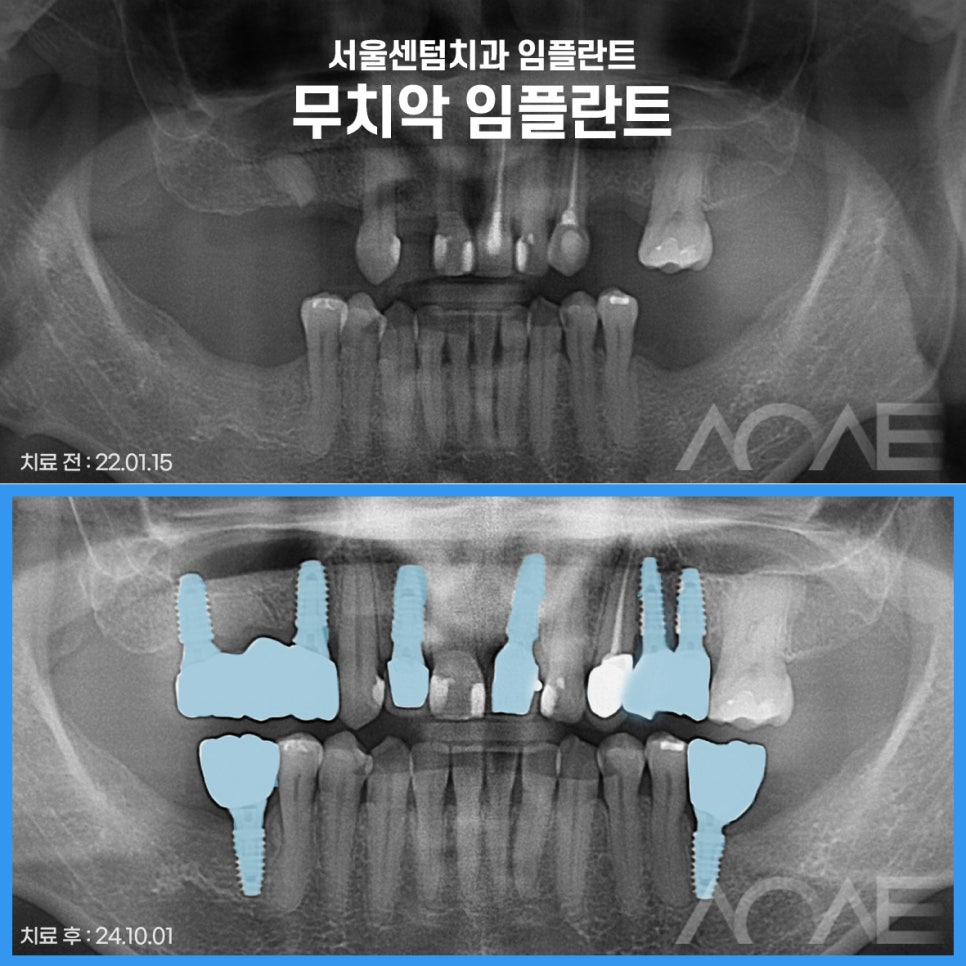

진료 받으신 분의 케이스를

한번 살펴보겠습니다.

*이해를 돕기 위해 동의 후 사용한 증례로

진료의 결과는 개인에 따라 달라질 수 있으니

주치의와 충분히 의논한 후 결정하시기 바랍니다.

잠원역치과 임플란트 케이스

치아를 상실하셔서

잠원역치과 서울센텀에

임플란트 수술을

받으러 오신 분의 케이스인데요.

치과의 두려움으로

방문을 미루시다가

다수의 치아를 잃어

임플란트를 해야할 것 같아

방문해 주셨습니다.

하지만 비용에 대한 걱정으로

고민이 많으셨는데요.

걱정을 덜어드리기 위해

만 65세 이상이셔서

저희가 먼저 보험 임플란트를

권해드렸었고, 비교적 적은 비용으로

진료를 받게 되셨습니다.

무치악이셔서 평소에 식사하기가

불편하셨을 것같은데 진료를

이제서야 받으러 오신 것을 보니

진료에 대한 두려움이

크신 분인것 같아 보였는데요.

실제로도 검진을 하고

수술 들어가기 전에 대화를 나눠보니

이제껏 참고 미루다가

식사할때 불편감과

진료에 대한 두려움을 함께 극복하려고

큰 마음 먹고 오셨다고 합니다.

심한 풍치로 흔들림이 심하고

예후가 안 좋은데

평소 불편한 점이 없었냐고 여쭤보니

잇몸이 좋지 않아 잦은 출혈이 보였고

흔들림이 심해 앞니로 베어먹기에 힘들어

고민이 많으셨다고 하셨습니다.

그래서 치아를 최대한 살리는 방향으로

고민을 해 보았으나,

이미 수명을 다한 치아로

안타깝지만 발치를 하기로 결정내렸습니다.

결론적으로 앞니 치아

하나를 발치하였으며

치아가 상실된 자리에

임플란트를 식립해드렸습니다.

그럼, 식립한 사진을 함께 볼까요?

위 사진은 임플란트 수술까지

마무리가 된 사진인데요.

개인의 잇몸상태를 분석하여

식립각도와 위치를 신경써서

안정적인 임플란트를 심어드렸고

반영구적으로 사용할 수 있도록

도와드렸습니다.